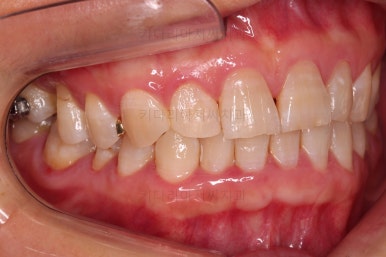

어금니를 뒤로 밀어주기 위해서 미니스크로와 브라켓, 철사를 이용해줍니다.

중간중간 장치 디자인이나 미니스크류의 위치를 바꿔주기도 합니다.

점점 자리가 확보되어가는게 보이시죠?

당연히 임플란트만 하고 끝내는 상황 보다는 치료기간이 길어지긴 하지만 어차피 보이지도 않는 부위이고, 입안의 약간의 이물감만 견딘다면 임플란트를 1개만 해도 되는 매우 좋은 치료라고 생각됩니다.